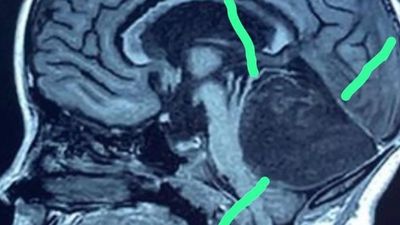

Një paciente e re nga rajoni i Jalal-Abad kishte një "masë të pazakontë" në trurin e saj, në të ashtuquajturën barkushe të katërt.

Ekipi kirurgjik drejtohej nga doktoresha Mitalipa Mamitov dhe ekspertët mbetën të shtangur kur kuptuan se “masa” në video ishte në fakt një fije floku, një metër e gjatë.

Ministria e Shëndetësisë ka publikuar imazhet në Facebook.